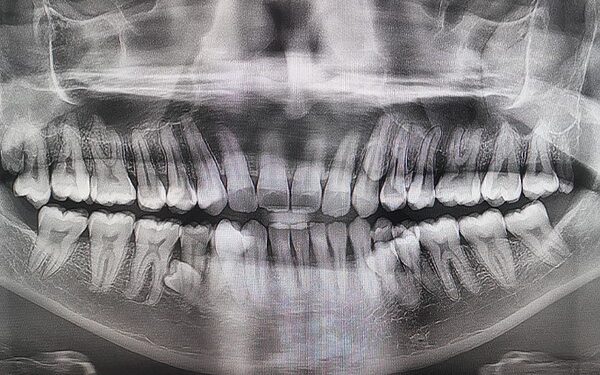

Convencido de que teria apenas três pares a mais que uma dentição normal, Prathab Muniandy chamou a atenção de especialistas por apresentar uma característica nada convencional. De acordo com exames efetuados, o homem possui 10 dentes a mais que uma pessoa adulta. No raio-X, foi mostrado que outros quatro dentes ainda não erupcionaram (que não romperam a gengiva).

Diante do cenário atípico, o malaio foi registrado no Guinness Book como o homem com mais dentes no mundo. O status somente foi possível após diversos dentistas decretarem a presença dos pares extras por meio de exames de imagem. Curiosamente, a presença das estruturas em excesso não atrapalha a vida de Muniandy, que afirmou que outras pessoas dificilmente notam a anomalia.